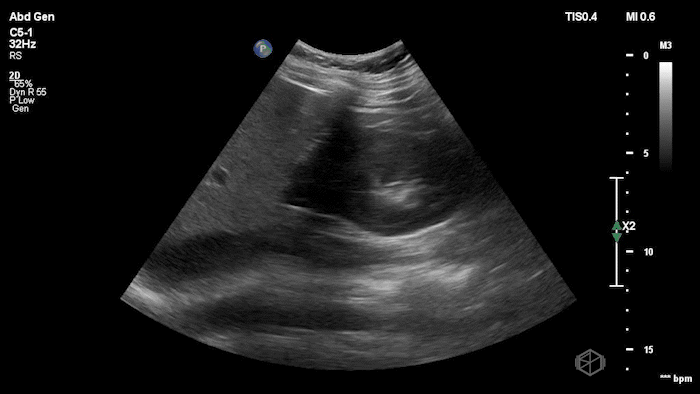

She grabbed the probe, and working with Dr. Zimmerman, saw the following:

There is moderate free fluid, no obvious pleural effusions. The bilateral ovaries are enlarged with multiple cystic structures. There are normal arterial and venous waveforms for both ovaries.

Initially it appears as though there is anechoic material above the liver and it does seem to make sharp angles. However, Dr. Konner and Dr. Maher utilized color doppler to evaluate the area and noted that it was simply the inferior vena cava. The patient ultimately had a CT scan that demonstrated no emergent findings.

Diagnosis: Potential false positive FAST - Inferior Vena Cava as a mimic of Free Fluid.

• Vessels can mimic free fluid. The IVC and other vascular structures sit right where we look for RUQ fluid and may appear anechoic in a single still frame. Use color doppler when not sure, free fluid will most commonly be at the caudal liver tip, and rarely just above the spine where the IVC sits.